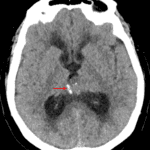

CT

- Pineal region mass with peripheral calcification

- Associated obstructive hydrocephalus